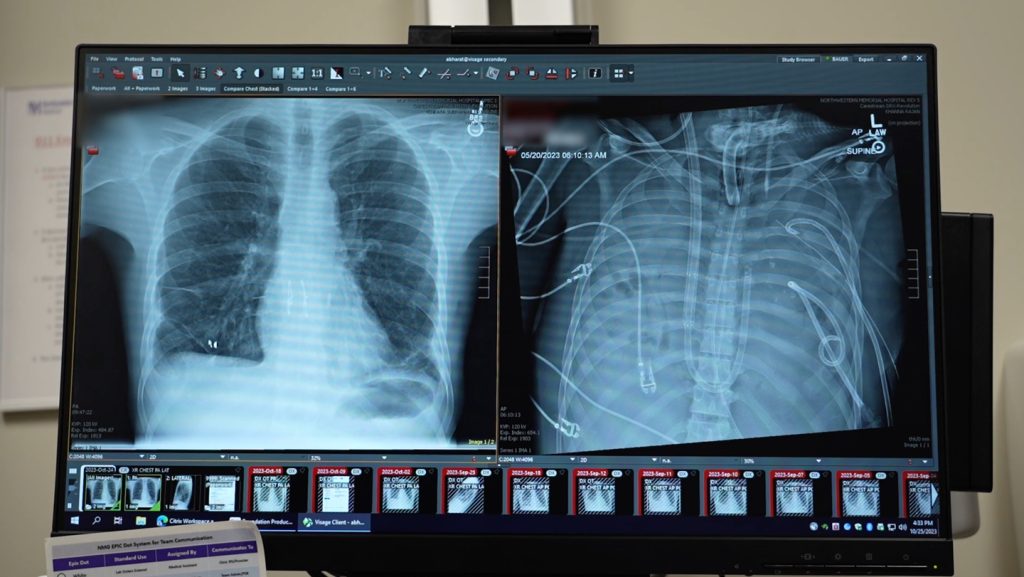

Imagine waking up one day with what feels like a bad flu. You cough, your chest hurts, and you think it’ll pass like it always does. But for a 33-year-old man from St. Louis named Alex – let’s call him that to give this story a personal touch – it didn’t. In 2023, he contracted influenza B, a nasty strain that hit hard. His body fought back, but the virus set off a chain reaction. Hospitalized, he battled not just the flu but a secondary infection with Pseudomonas aeruginosa, a stubborn bacterium resistant to most antibiotics. This bug invaded his bloodstream, spreading like wildfire. His lungs, the vital organs meant to oxygenate his blood and keep him breathing, were deteriorating under the assault of infection and his own immune system’s overzealous defense. Doctors at his hospital watched helplessly as his condition worsened. “He was not getting better,” recalls Ankit Bharat, chief of thoracic surgery at Northwestern University Feinberg School of Medicine in Chicago, the surgeon who would become a key figure in Alex’s lifeline. Bharat speaks with a mix of professional detachment and deep empathy – he’s seen too many patients in similar straits, often with devastating outcomes. Tests showed Alex’s lungs were beyond repair; they wouldn’t recover. He was actively dying, gasping for air that his body couldn’t process on its own. This wasn’t just a medical case; it was a human tragedy unfolding in real-time. Alex, a father, a friend, a worker, faced the unthinkable. His loved ones gathered at his bedside, hoping for a miracle, fearing the worst. In that moment of crisis, Bharat and his team decided to push boundaries, blending innovation with urgent care to give Alex a fighting chance.

The path wasn’t straightforward. Lung transplants are uncommon miracles, but they’re delicate. With infections like Alex’s active Pseudomonas in his system, no transplant center would risk it – the bacteria could kill the donor lungs instantly. Yet, leaving him on a ventilator wasn’t sustainable; his damaged lungs couldn’t handle it. Bharat, a seasoned surgeon skilled in transplants for patients ravaged by COVID-19 or similar scourges, knew they needed something radical: remove the lungs entirely and keep him alive artificially until an organ became available. This inspired the creation of a custom artificial lung system, a feat of engineering and medicine that could sustain life in ways conventional tech couldn’t. Visualizing it, Bharat saw tubes, shunts, pumps – devices to draw blood from the right side of the heart, oxygenate it by stripping out carbon dioxide just like natural lungs, and then shunt it back to the heart’s left side for circulation. It was proof-of-concept turned into a life-saving procedure. For Alex, it was hope. His family clung to updates, praying for his pain to end. The doctors felt the weight too; one wrong move and he’d be gone. But in the chaos of intensive care, with beeps and alarms, Bharat’s team prepared, driven by a shared belief that innovation could rewrite Alex’s ending. They weren’t just removing lungs; they were bridging a gap between death and rebirth, transforming cold machinery into a conduit for human resilience.

Delving into how this artificial lung system worked reveals its brilliance and humanity. Unlike earlier attempts with extracorporeal membrane oxygenation (ECMO), a form of life support that pumps oxygenated blood but often strains the heart, this setup truly mimicked the lungs’ double role: oxygenation and proper cardiac support. Picture it – blood exits the right atrium, gets pumped through an oxygenator to refresh it, removing evil carbon dioxide and infusing life-giving oxygen, then flows seamlessly back to the left atrium. Pumps handled the flow, ensuring the heart didn’t overwork. In the operating room, surgeons crafted this like artists: shunts to channel blood, tubes to connect vessels, all orchestrated to keep Alex’s body functioning as if his lungs were intact. For Bharat, it was a testament to collaboration between engineers and doctors, turning abstract designs into tangible saviors. Alex, under anesthesia, couldn’t feel the procedure, but post-op, he must have sensed a strange stability, his body humming along mechanically. The team monitored every beat, every saturation level, their faces etched with tension and hope. It wasn’t just machines; it was a symphony of precision, where one glitch could shatter the harmony. This system, reported in Med on January 29, proved a true artificial lung could buy time, keeping patients alive until transplants. For Alex, it was a bridge over turbulent waters, whispering that survival was possible. His nurses, caring hands in the night shifts, checked vitals with quiet encouragement, turning the sterile ICU into a space of unspoken support.

The 48 hours that followed were a marathon of anticipation. With Alex’s diseased lungs removed and the artificial system in place, doctors watched as his infected right side of the heart began to heal shockingly fast. Contrary to expectations of weeks for the bacteria to clear, removing the bacterial breeding ground – the lungs – sped recovery like wildfire doused by water. Infections vanished as if evicted. Meanwhile, the transplant list beckoned anew. Alex’s bloodwork improved, his body stabilized. Worry crept in during that limbo; what if an organ didn’t arrive? His loved ones visited, holding his hand, sharing stories to keep his spirit alive. Bharat recalls the quiet nights, the team sipping bad hospital coffee, debriefing tirelessly. Then, fortune smiled: an organ matched immediately, a gift from a donor’s legacy. The transplant surgery unfolded smoothly, lungs reattached, blood flowing naturally once more. Now, over two years later, Alex thrives. His heart beats strong, lungs function normally – he’s back to work, family time, life’s simple joys. Doctors marvel at his progress, a living testament to medical ingenuity. Yet, beyond stats, it’s the human cost that lingers: Alex’s gratitude, perhaps shared in quiet moments; the donor family’s solace knowing lives like his were saved; Bharat’s satisfaction in mending what seemed broken.